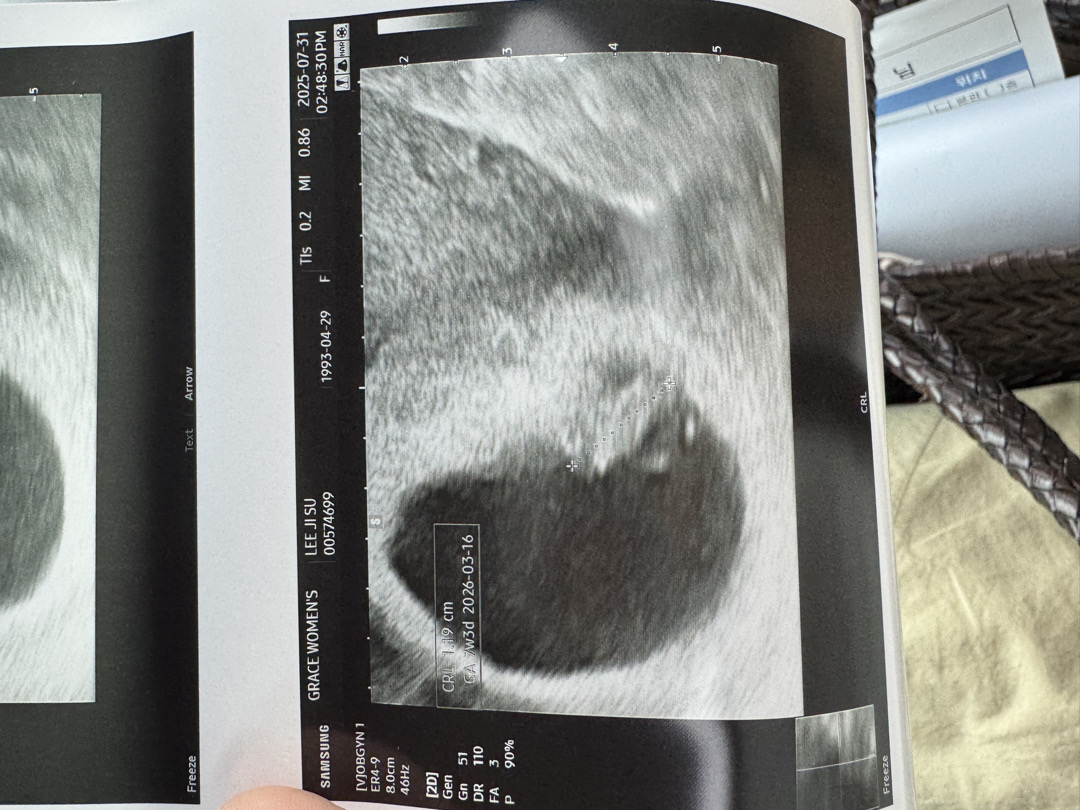

7주3일초음파

갈때 마다 넘떨리는데 잘 있어서 얼마나 다행인지 평안하게 있어야하는데 걱정쟁이맘입니다